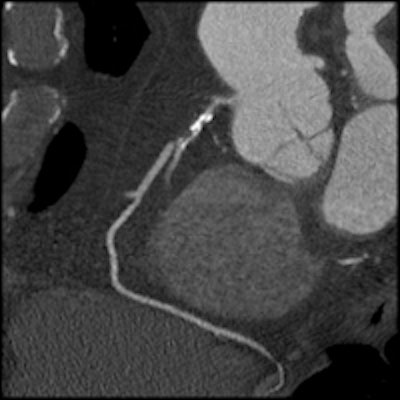

Same patient as above. Image shows the circumflex but demonstrates how use of the Discovery HD750 scanner allows clear visualization of the short stenosis despite the stent and high level of calcium in the arteries.At Roobottom's institution, they run the HD scanner in both modes depending on the calcium score. Low calcium scores receive conventional imaging, while high calcium scores receive HD imaging.